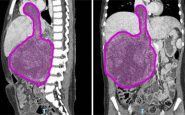

Questa rara estensione del tumore – ha spiegato l'ospedale – si verifica in appena il 4-10% dei casi di nefroblastoma. Prima dell’intervento Sara è stata sottoposta a sei cicli di chemioterapia, eseguiti dal team di oncologi guidati dal professor Franco Locatelli, per ridurre la massa tumorale e facilitare l’operazione.

La fase preparatoria pre-chirurgica si è avvalsa di tecniche all’avanguardia di diagnostica per immagini come l’elaborazione 3D del tumore da asportare realizzata dall’unità di Imaging avanzato cardiotoracovascolare e fetale".